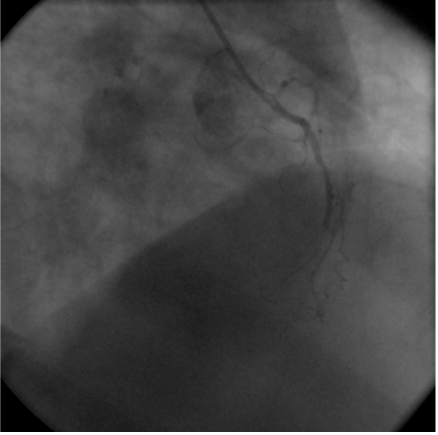

A 55-year old man was transferred from one of our referring hospitals with early post infarct unstable angina, having chest pain in the right side of the chest radiating to the right shoulder and the back, following an anterior ST-elevation myocardial infarction for which he had received thrombolytic therapy. He was a known case of dextrocardia with Kartagener syndrome, diabetic and smoker. Physical examination was unremarkable except for findings consistent with dextrocardia. Apart from raised troponine-I and blood sugar, his routine laboratory tests were within normal values. 12-lead Electrocardiogram (ECG) showed a negative P wave lead-I and aVL and positive P and R waves in aVR together with Q waves in inferior leads. Reversed chest leads showed QS in V1-V3 with ST depression in V4-V6 associated with deep T wave inversion. Chest X-ray revealed dextrocardia with a right-sided aortic knob as well as gastric bubble. Echocardiography revealed left ventricle ejection fraction of 40% with hypokineses correspondent with ischemia in left anterior descending artery (LAD) territories and no significant valve disease. Cardiac catheterization was performed via the right radial artery using mirror-image views and standard Judkins catheters. A 5 French (Fr) angulated pigtail catheter was through the right-sided aortic knob into the left ventricle. The 300 left anterior oblique (LAO) ventriculogram (Figure 1) showed anterior wall hypokinesia and severe hypokises/akineses of the apex and the inferior wall with an ejection fraction of 40%. The ostium of the right coronary artery (RCA) was easily engaged by gentle counterclockwise rotation and slightly withdrawal of a 5 Fr Judkins right 4 cm (JR4) diagnostic catheter in right-anterior-oblique (RAO) and RAO-cranial views showed 100% lesion at mid-RCA segment (Figure 2). The ostium of the left main coronary artery was also cannulated using a 5 Fr Judkins left 4-cm (JL4) diagnostic catheter in a RAO view. The selective left coronary angiogram revealed a>70% tubular stenosis in the middle segment of LAD artery and a patent left circumflex (LCX) artery (Figure 3). Adhoc-PCI to LAD was performed with the use of 5 Fr JL 3.5 guide catheter and a 0.014” balanced middleweight (BMW) guide wire. Two overlapping drug-eluting stents (Xience Prime 2.5x28mm and Promus Element 2.25x12mm) were directly deployed at the site of the lesion in the middle segment of the LAD artery with good angiographic result (Figure 4). The patient experienced an uneventful post-PCI course and was discharged on the following day. He was free of angina on clinical follow-up.

Figure 4 Post angioplasty left coronary angiogram in postero-anterior/cranial injection showing normally flowing vessel. The image is mirror image to conventional poster-anterior/cranial projection for the left coronary system in normal situation.